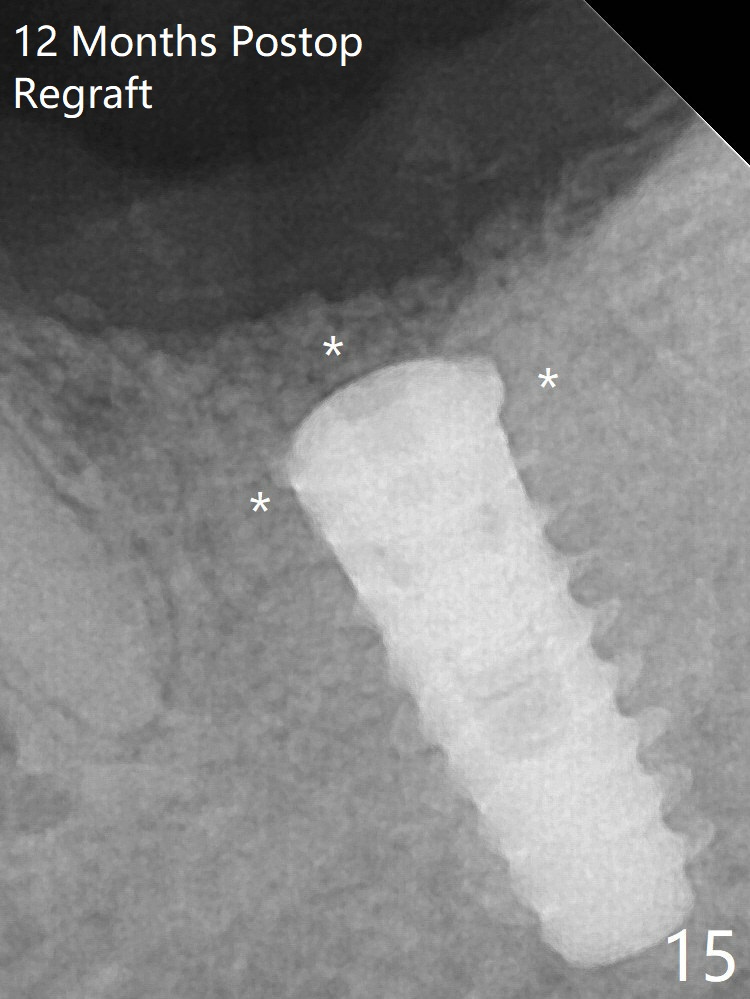

The implant is removed, cleaned with Titanium brushes and H2O2 in vitro and repositioned 12 months postop (Fig.14: arrow (gaps: post granulation tissue removal)). The gaps are regrafted with sticky bone and covered with PRF membrane and Cytoplast.取出植体,钛刷清洗,即刻植入,种深些(图十四:箭头),冠部螺纹两旁有间隙(*);放置愈合帽,最后表浅放置粘性骨粉(图十五:*)。覆盖不可吸收膜,